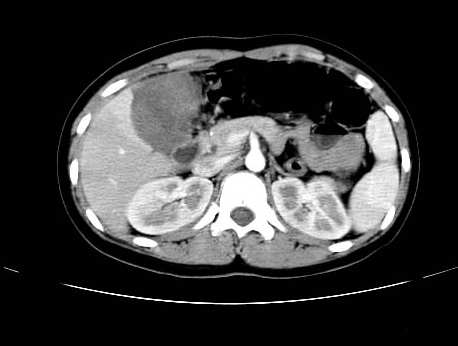

女 16岁  右上腹痛一天,无其他不适

肿块最大径位于十二指肠降段与水平段移行处,并且与肝脏压迹呈“0”形征,可以考虑位于肝外并与胃肠道关系紧密,考虑胃肠道间质瘤(gist)可能较大,须除外神经节起源肿瘤。

肿块与十二指肠关系密切,支持间质瘤诊断.肝脏与结肠均为受压改变.

右下腹巨大肿快,密度不均匀,内见坏死低密度区,边界清楚,与周边胀器明显有分界,未见强化,多考虑来源于间叶组织的良性肿物.

病灶巨大,少部分向肠腔内生长,大部分向长腔外生长。其密度不均匀,增强显示明显不均匀强化,并见有大片状始终不强化的不规则坏死液化区。虽然病灶中上部形态尚可,病人又如此年轻,但中下部形态、密度、强化特点强烈提示为恶性病灶。综上,我考虑本病例为:恶性胃肠道间质瘤。